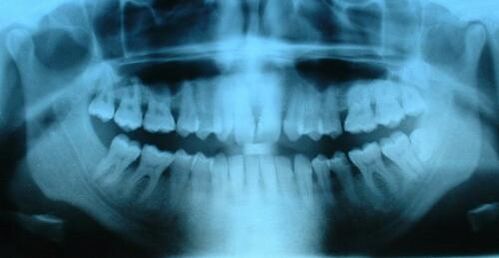

В норме у человека имеется от 28 до 32 зубов. Различают молочные (временные) и постоянные зубы.

Во временном прикусе (молочные зубы) присутствует 8 резцов, 4 клыка и 8 моляров — всего 20 зубов. У детей они начинают прорезаться в возрасте от 3 месяцев. В период от 6 до 13 лет молочные зубы постепенно заменяются постоянными.

Постоянный прикус состоит из 8 резцов, 4 клыков, 8 премоляров и 8—12 моляров. В редких случаях наблюдаются дополнительные, сверхкомплектные зубы (как молочные, так и постоянные)[1]. Отсутствие третьих моляров, называемых «зубами мудрости» является нормой, а сами третьи моляры увеличивающимся числом учёных уже считаются рудиментом, но это на данный момент спорный вопрос.

Приблизительно в 6 - 8 месяцев начинает прорезываться центральный нижний резец. За нижними резцами следуют верхние резцы, за ними - клыки и, наконец, моляры. В возрасте от двух с половиной до трёх лет этот процесс завершается. У ребёнка образуется полный комплект из 20 молочных зубов, в каждом ряду - 4 резца, 2 клыка и 4 моляра.

В 6 лет резцы заменяются постоянными зубами, появляются постоянные первые моляры. Приблизительно в 9 лет клыки также заменяются на постоянные зубы. В 12 появляются вторые постоянные моляры, а молочные моляры окончательно заменяются на премоляры. Наконец, в 18 появляются третьи моляры - зубы мудрости.

Время прорастания всех зубов может значительно отличаться. Например, у 25% людей зубы мудрости не вырастают вовсе. Это вызвано уменьшением челюсти в процессе эволюции. По этой же причине у 50% людей проросшие зубы мудрости оказываются зажатыми (стиснутыми под десной). В таком случае их необходимо удалять.